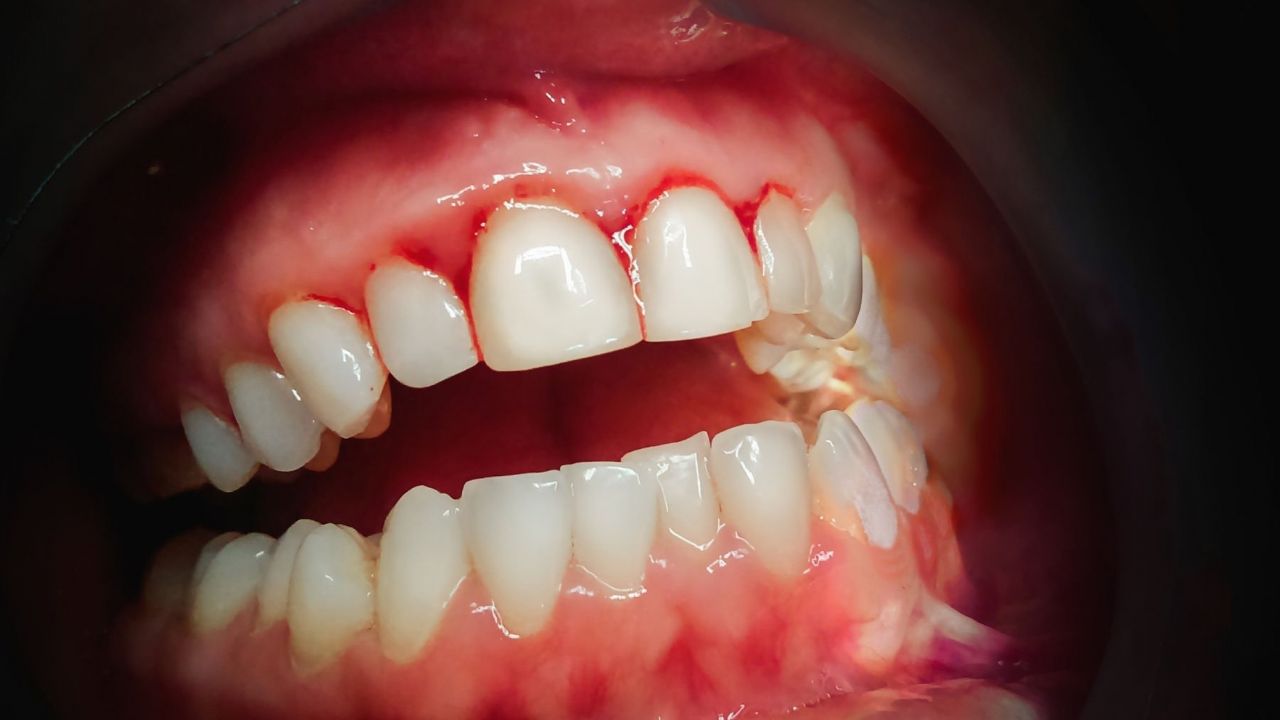

O sinal mais marcante é a necrose das papilas interdentais, frequentemente descrita como uma aparência em “cratera”, resultado da destruição tecidual localizada. Sobre essas áreas necrosadas, observa-se a formação de pseudomembranas acinzentadas ou esbranquiçadas, que recobrem as lesões e podem ser facilmente removidas, revelando um tecido subjacente intensamente dolorido e sangrante.

O sangramento gengival ocorre de forma espontânea ou ao mínimo contato, refletindo o grau de inflamação e fragilidade vascular local.

A identificação precoce desses sinais clínicos é determinante, pois o atraso no diagnóstico pode favorecer a progressão da doença para periodontite necrosante ou até estomatite necrosante, condições que representam risco significativo de destruição tecidual extensa e maior morbidade.